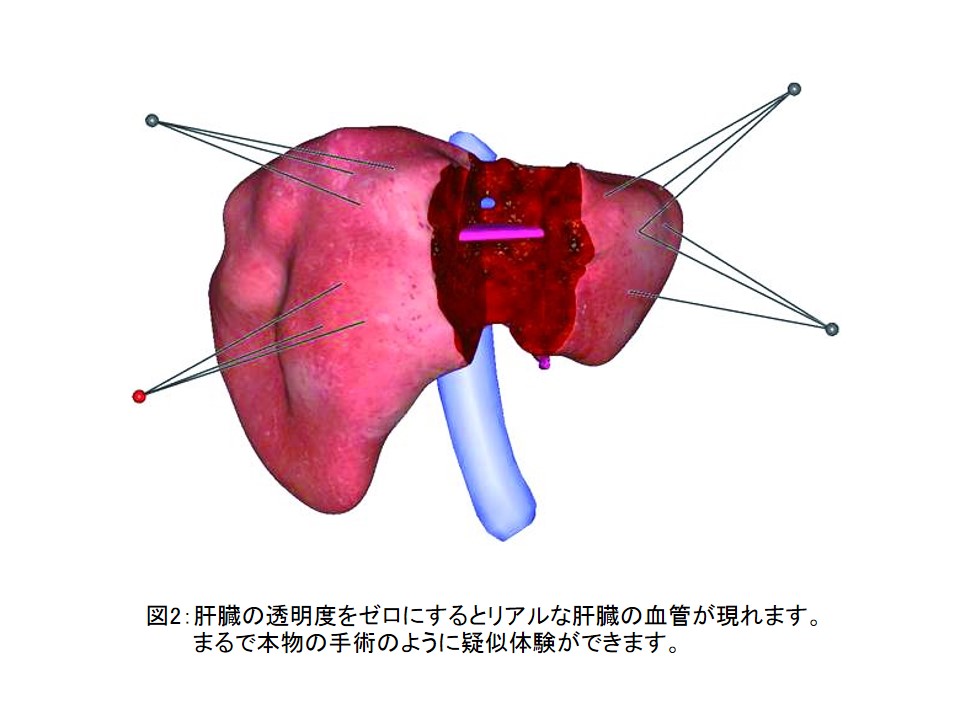

医療用3Dワークステーションで学ぶ 脳神経外科手術戦略。医療用3Dワークステーションで学ぶ 脳神経外科手術戦略。脳神経外科 Vol.50 No.4: STA-MCAバイパス術―日本が世界に誇る技。パックご飯秋田米100%。大阪公立大学大学院医学研究科 脳神経外科学教室とコラボ 新しい。タグ「Opening the future ~医用画像処理のネクストステージ。医療用3Dワークステーションで学ぶ脳神経外科手術戦略シミュレーションこちらは裁断済みの商品です。定価:11000円。ITEM2024レポート 〜Workstaion編〜 | MRIfan.net。教科書『Robotic Surgery Devices in Surgical Specialties。ziostation2 | アミン株式会社。ムービーコンテンツ – AESCULAP® Orthopaedic Academy online。ITEM2024レポート 〜Workstaion編〜 | MRIfan.net。。ITEM2024レポート 〜Workstaion編〜 | MRIfan.net。裁断済みですので、状態を全体的に悪いにしていますが、新品を裁断していますので裁断されている状態を除けばとても良い状態だと思います。第18回日本整容脳神経外科学会(JSAN2025)/第34回脳神経外科